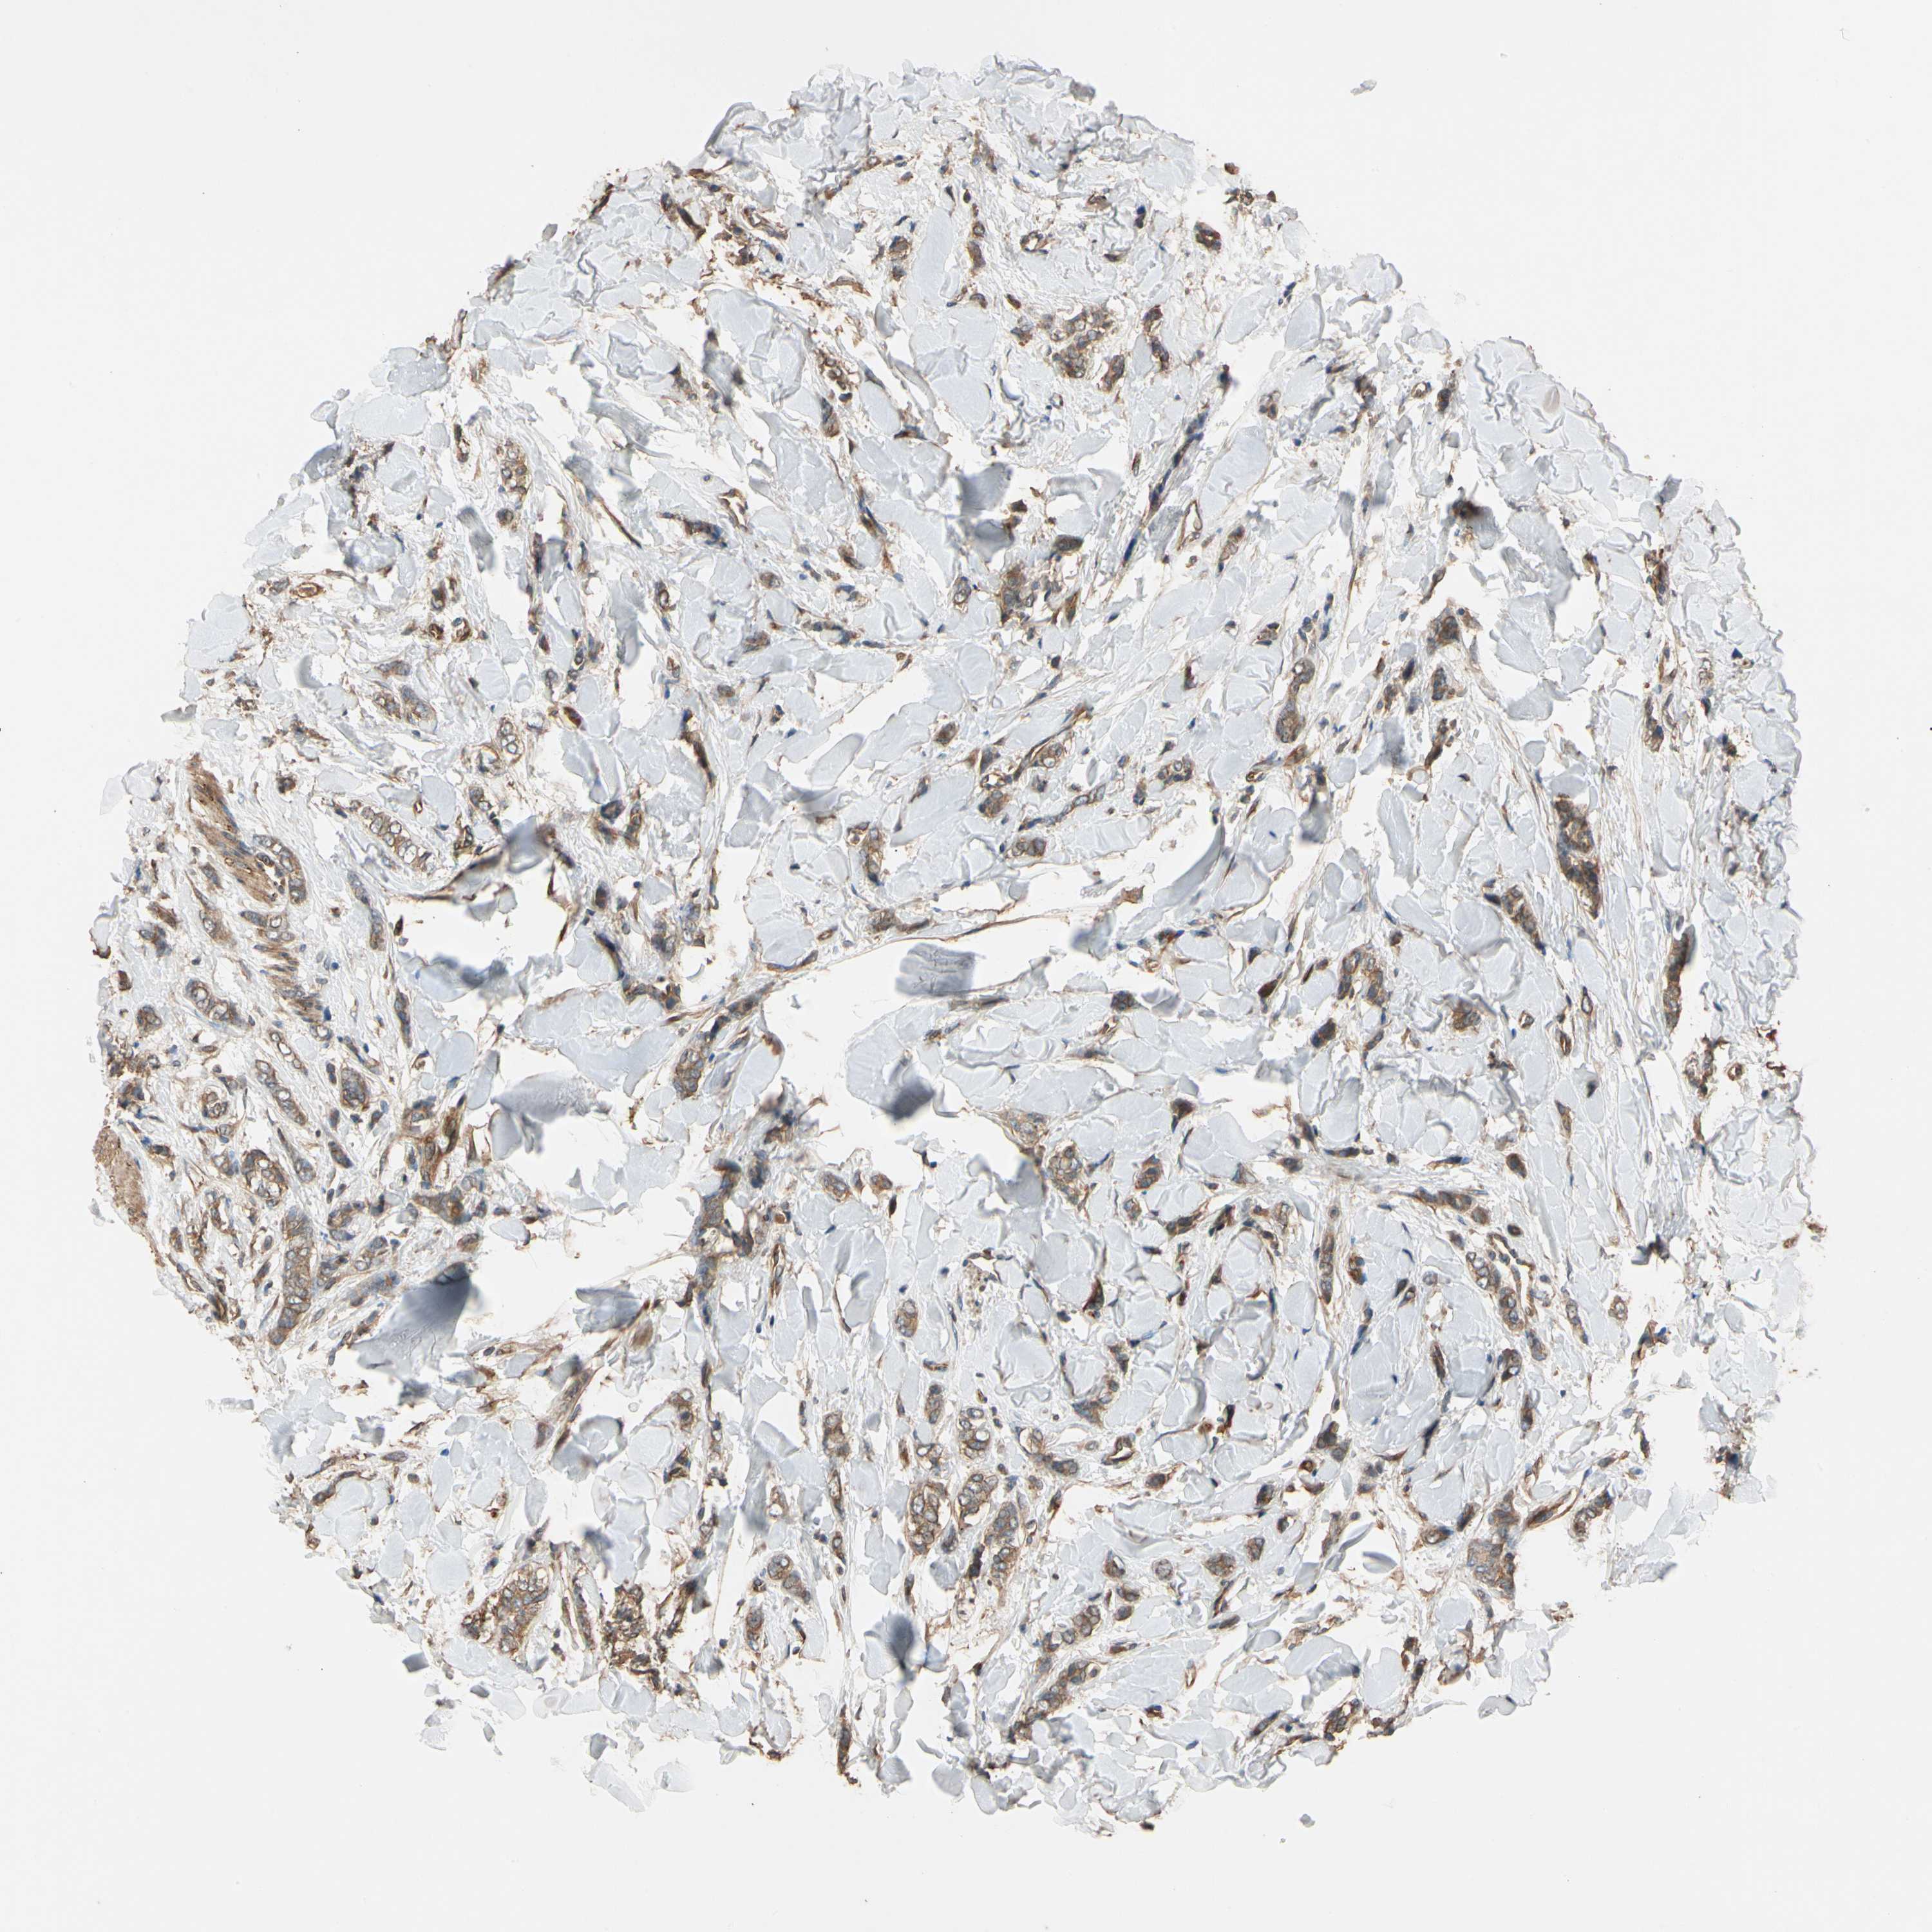

CANCER BREAST CANCER Show tissue menu

BRCA TCGA BRCA VALIDATION PROTEIN EXPRESSION